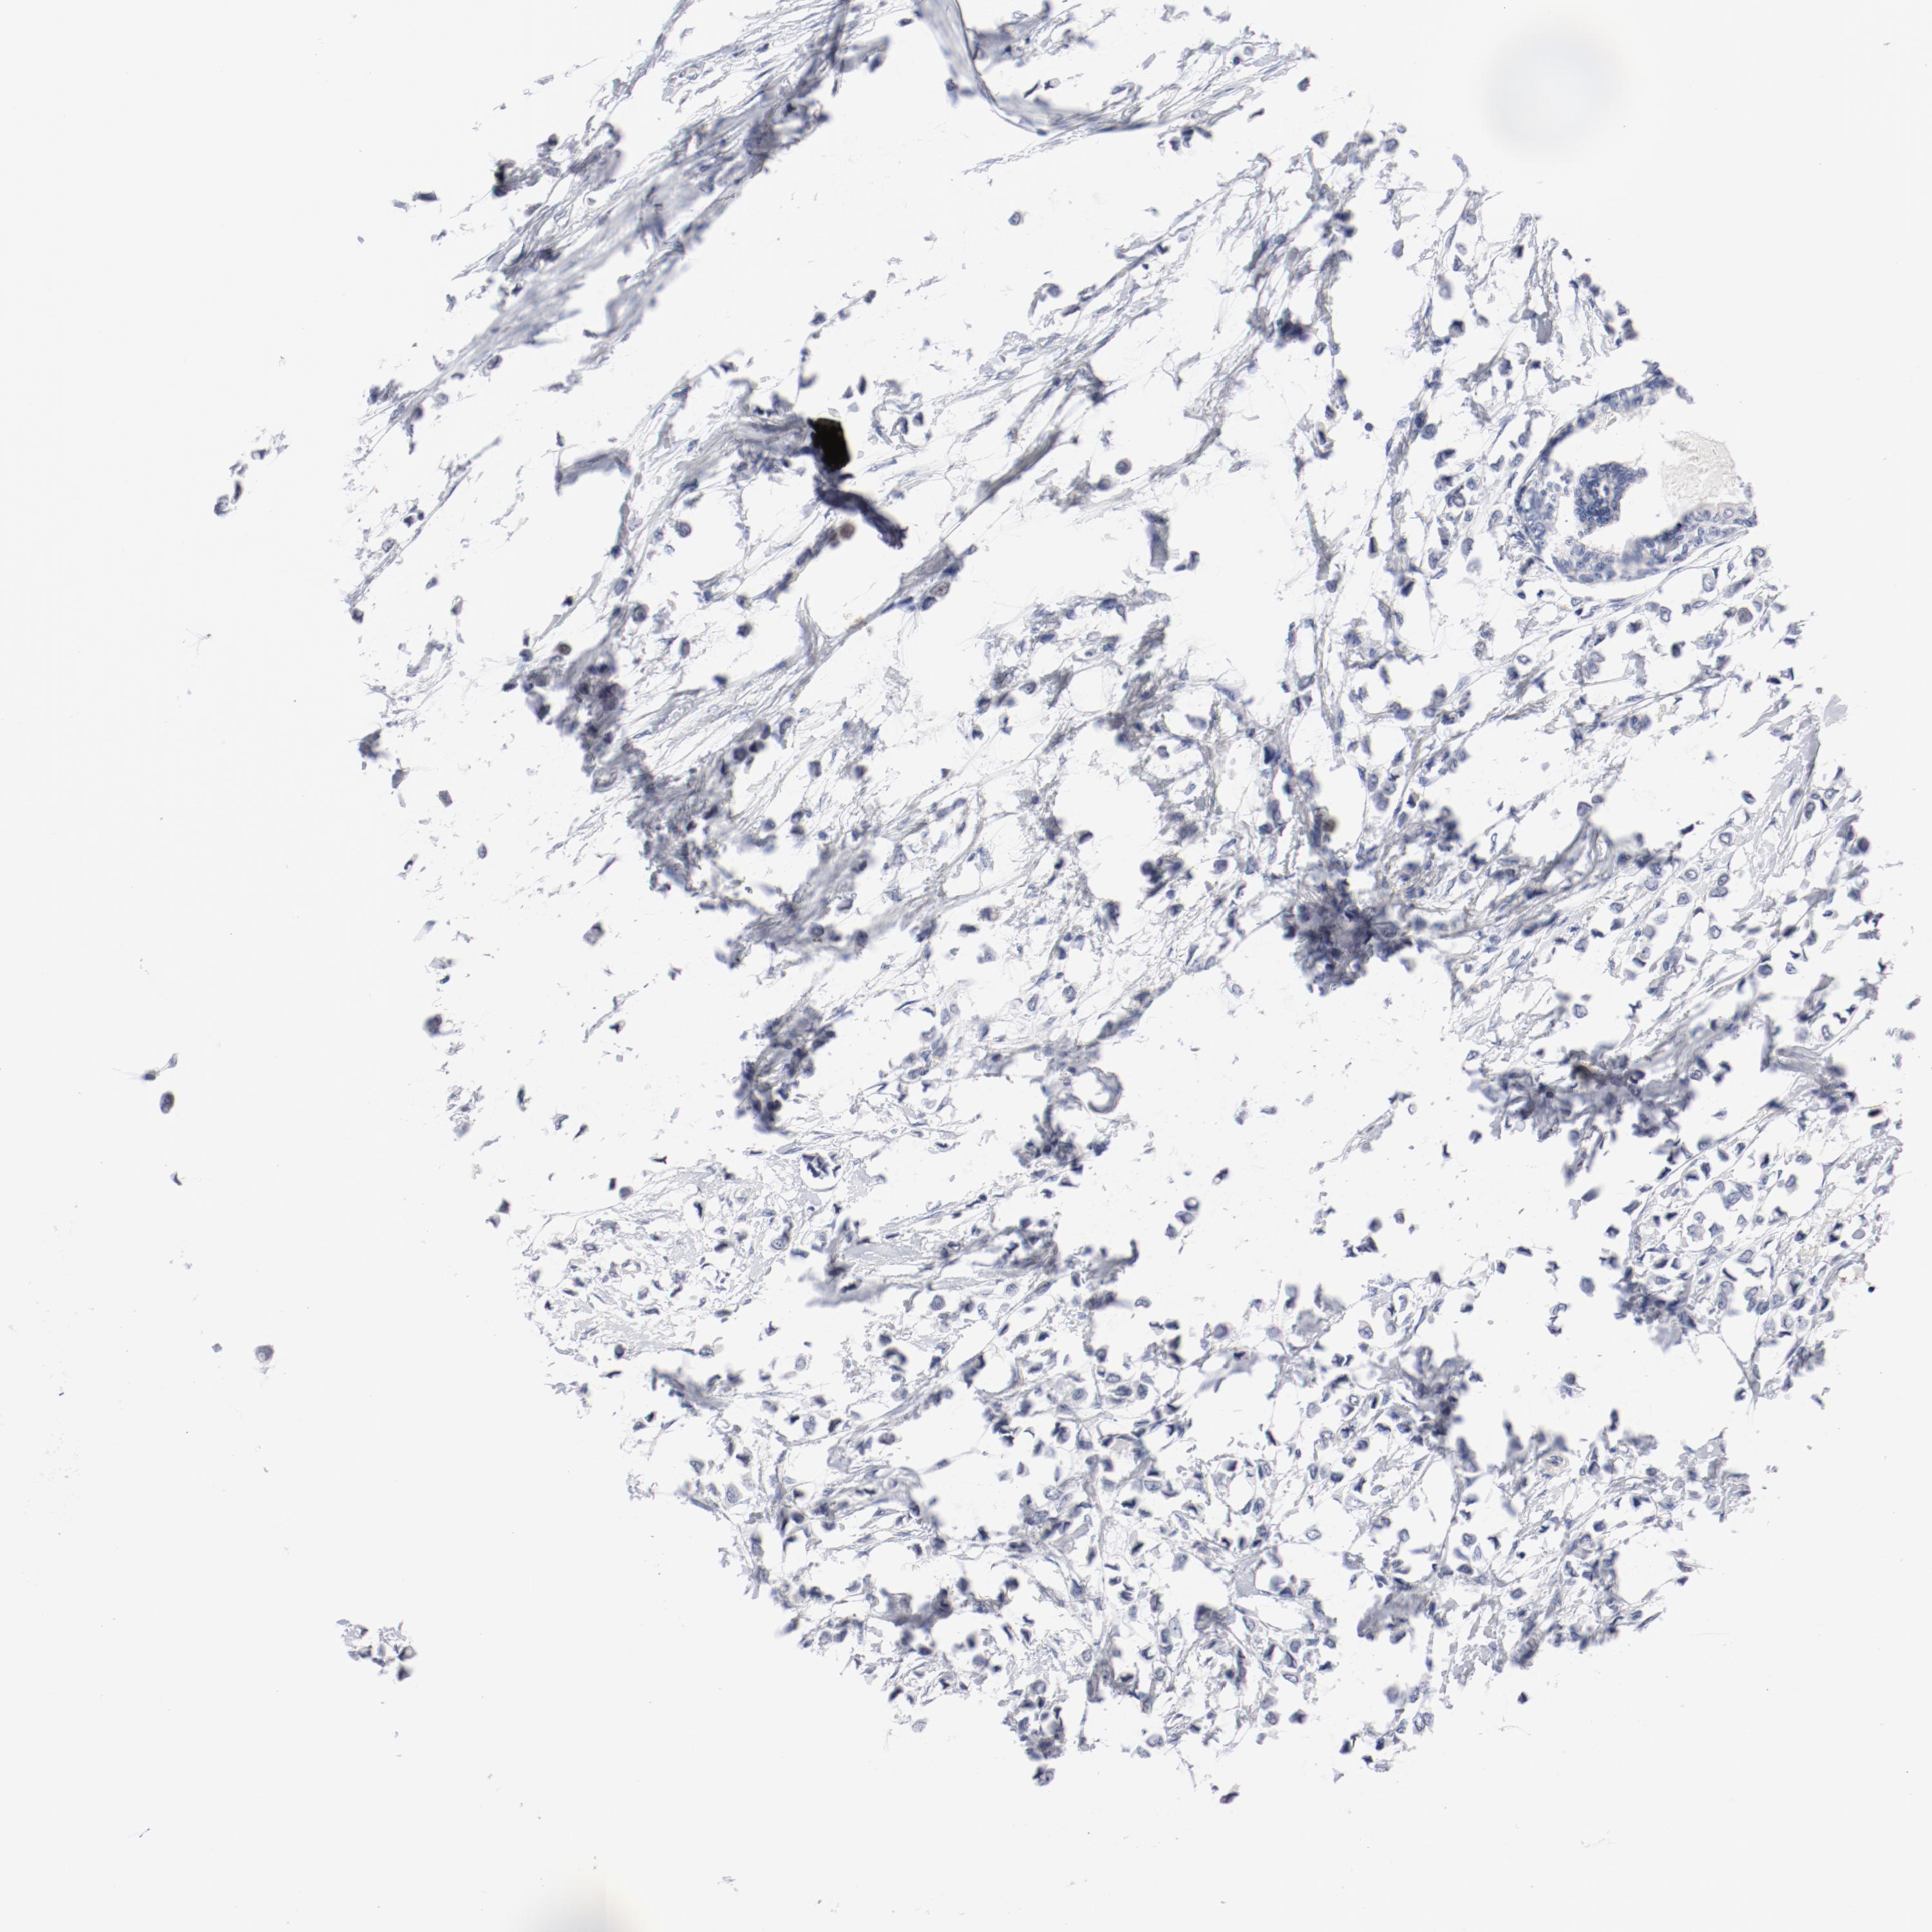

CANCER BREAST CANCER Show tissue menu

BRCA TCGA BRCA VALIDATION PROTEIN EXPRESSION